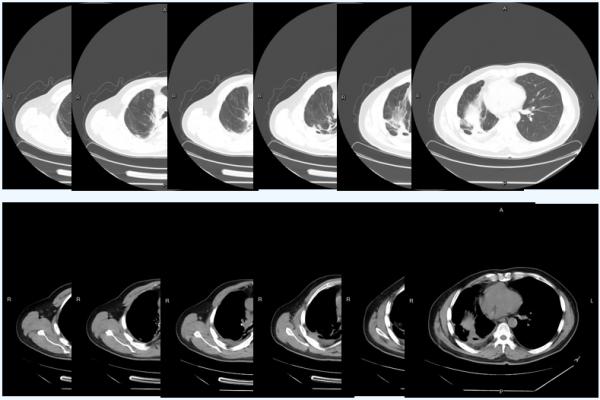

2021-2-18複查CT:

1、肺癌術後改變,

吻合口周圍不規則軟組織影伴空洞形成,與原片(2020-11-18)比較,範圍較前縮小;其內空洞較前縮小;右側胸腔積液較前減少。

2、右肺炎症實變較前範圍縮小;右肺內結節變化不大。

3、縱隔內、右側心膈角及雙側腋下多發淋巴結輕度腫大。

對免疫單藥及聯合治療期間安全性的監測發現,患者甲狀腺功能和心臟功能維持在正常範圍之內,鱗狀細胞癌相關抗原也維持在穩定區域。

從下圖可以看出,患者在免疫治療前腫瘤大面積佔位,免疫聯合治療期間快速縮瘤,後續免疫單藥維持治療帶來持續獲益。

患者於本院治療前、接受替雷利珠單抗+化療後及替雷利珠單抗單藥治療對比